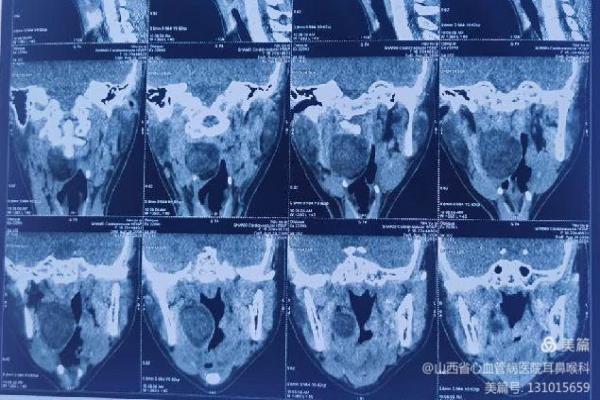

患儿就诊时,自觉偶有憋气及咽痛。张浩杰主任第一时间接诊,经过仔细查体、喉镜和颈部影像学CT与MRI检查后,发现患儿咽腔明显受压,口咽部椎前间隙巨大肿瘤。